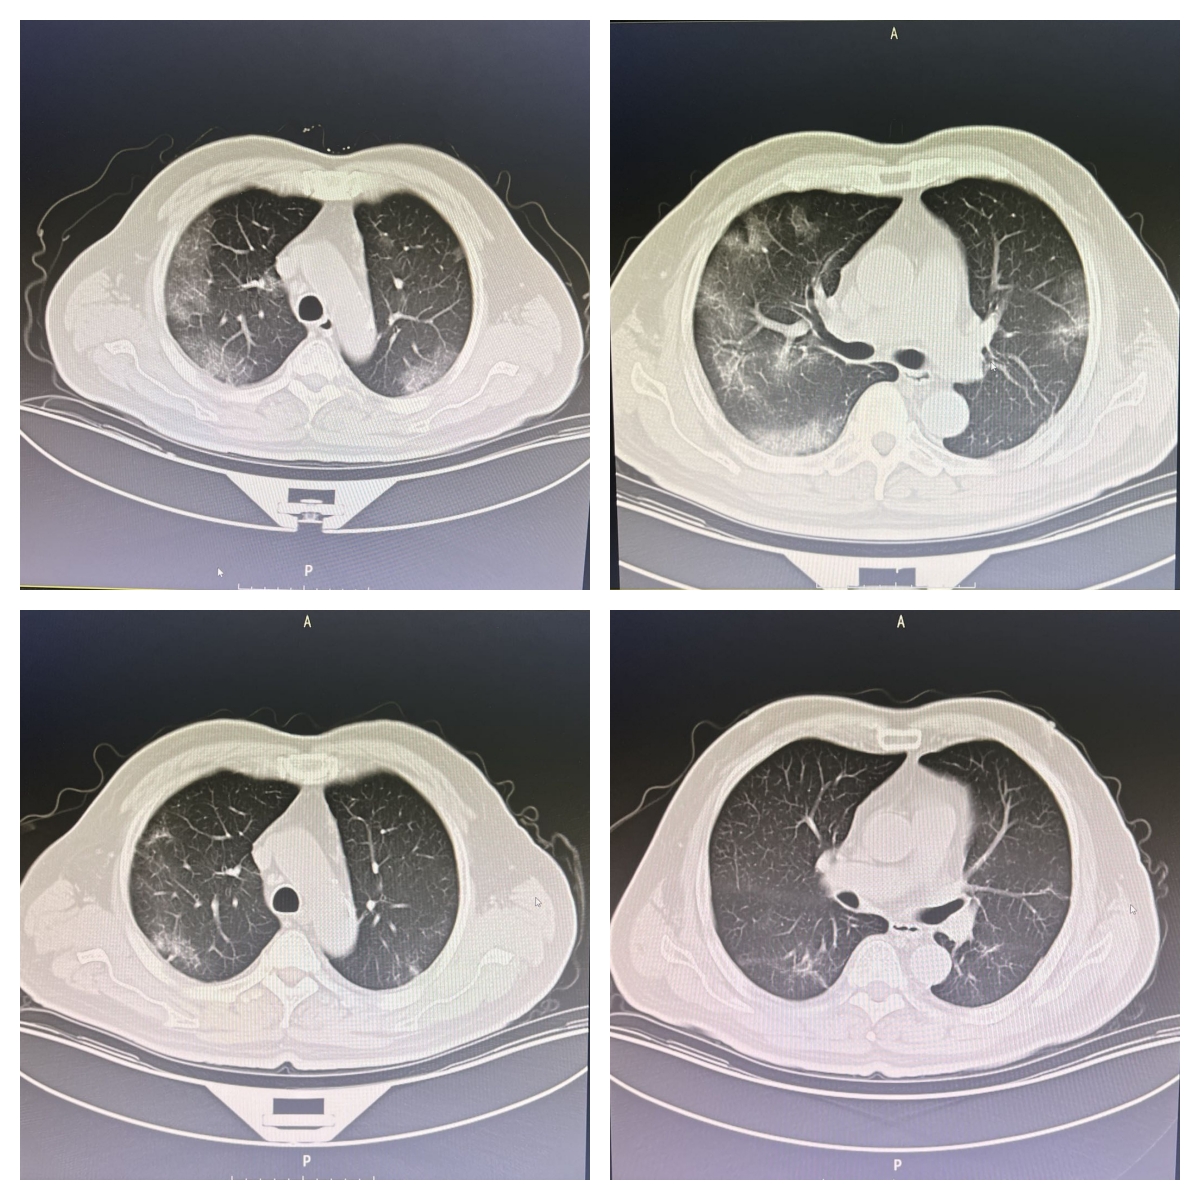

“我小孙女经常在网上刷什么快手、抖音,老是跟我说这个yyds、那个yyds,我问她啥叫yyds啊,她告诉我就是‘永远的神’,就是非常棒的意思。今天我也要说济宁市中医院肺病科的医生护士们技术一流,yyds!”家住市区的张老爷子病愈后,由衷赞叹济宁市中医院肺病科的医护人员。 事情还得从上个月说起,当时张老爷子冒雨后开始咳嗽,咳痰,无发热,后来开始咳鲜红、暗红色血痰,并且量比较多。他没当回事儿,自己跑去药店买来“头孢类”药物自行治疗,治疗了接近一周未见明显好转。并且出现了气短、喘息症状,食欲差、睡眠质量差、小便频繁、大便干燥、乏力。 张老爷子现年79岁,平素身体较硬朗,30年前曾患间质性肺炎,间断服用“银杏叶口服液、辅酶Q10”。入院后见舌质暗红、苔薄白。肺病科主任刘璐为其进行一系列检查后,中医诊断为咳嗽阴虚肺燥证,西医为支气管肺炎合并新冠病毒感染。

病愈后,张老爷子非常开心,“到我这个年龄段,虽然说生死看淡了,但是身体上一系列不舒服的症状出现,并且越来越重时,心里还是感觉到了恐慌。是市中医院肺病科的医护人员们精心护理,不断调整治疗方案,才让我这把老骨头健健康康地保住了。真的谢谢你们!” 刘璐提醒,在日常生活中,绝大部分人已经能做到戴口罩、勤洗手、保持一米距离、接种疫苗等预防呼吸道感染的一些基本措施。但是对于肺炎期和康复期的患者,除了必要的营养支持和充足休息外,还要经常清理呼吸道,鼓励患者每隔一小时进行深呼吸和有效咳嗽。影像上感染期或血氧饱和度低的患者还要进行配合俯卧位通气。恢复期要适当活动,坚持呼吸功能锻炼至少要持续4-6周,以提高肺功能的目的。 同时需要提醒大家,导致肺炎发生的病原体多种多样,生活中“吃点消炎药”仅能治疗一部分细菌性肺炎,对支原体、衣原体、呼吸道合胞病毒、柯萨奇B病毒等引发的肺炎无效。此外,肺炎的严重程度也会因人而异,尤其对于老年患者,其本身免疫力低,基础疾病多,咳嗽、咳痰等肺炎症状可能不典型,如果得不到及时的诊治就会拖延病程。 刘璐建议,如果咳嗽加重,咳痰量增加,出现痰中带血,短期内再次发热,气短、呼吸困难、胸痛等症状明显加重,以及咳嗽超过2周,老年患者出现精神萎靡、食欲减退等,要及时去医院就诊,以免延误最佳治疗时机。 |